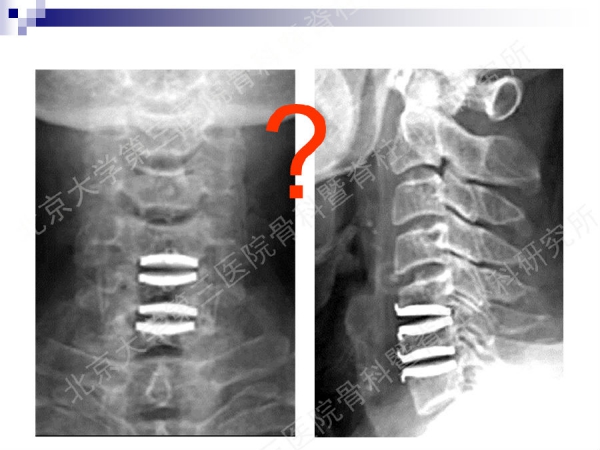

今天,在北京大学第三医院骨科暨脊柱外科研究所刘忠军教授分享的《颈椎人工椎间盘置换手术注意问题》课件中,他将通过大量影像资料、临床研究数据和长期随访结果,给大家介绍现阶段最重要的颈椎非融合技术——人工椎间盘置换术的适应证、禁忌证和其他需要密切注意的一些问题,提醒同道关注与手术技术及内植物相关的尺寸、终板顺列、中心轴线顺列等问题,严格把控手术指征,规范、精准地开展颈椎人工椎间盘置换手术,保障手术疗效。